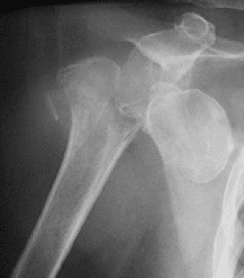

Onderzoeken

Op de raadpleging zal u klinisch onderzocht worden om uw pijn en functiebeperking te beoordelen.

Om de kwaliteit van het bot en van de rotatator cuff te beoordelen zal een aanvullende radiografie, arthro CT-scan en soms ook een NMR verricht worden.

In overleg kan dan eventueel beslist worden om een schouderprothese te laten plaatsen. Het type prothese dat voor u het meest aangewezen is wordt dan bepaald.